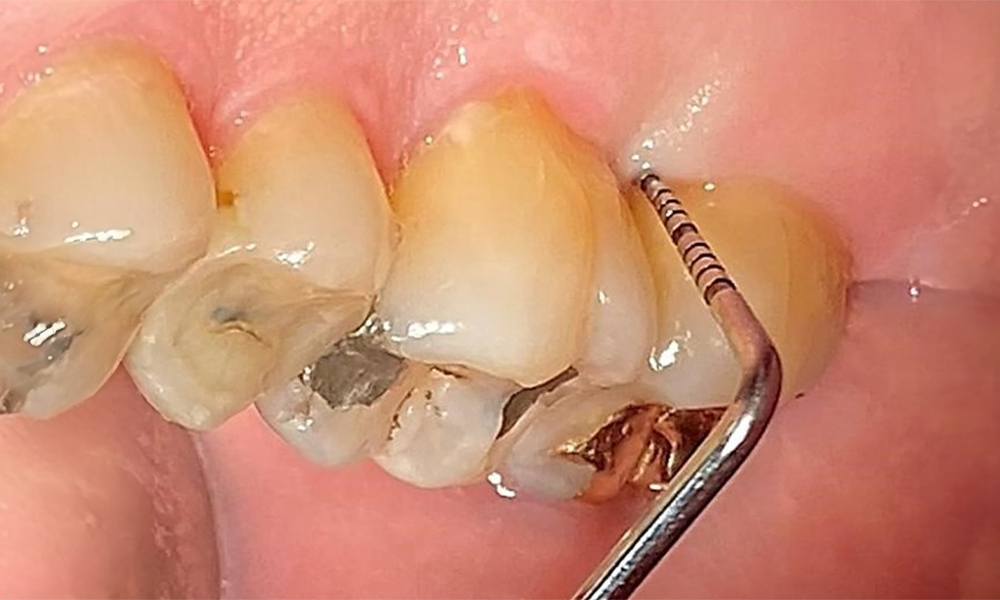

Occlusal view of the maxilla. Insufficient amalgam filling of 14 with a marginal gap.

Fig. 5 Occlusal view of the maxilla. Insufficient amalgam filling of 14 with a marginal gap. © Dr R. Krapf

The patient has a full dentition with 28 teeth, which includes amalgam and composite fillings in the molar and premolar regions. There is a visible clinical marginal gap present on tooth 14. Tooth 27 has an adequate gold inlay. There are also generalized attritions and abrasions. (Fig. 2, Fig. 3, Fig. 4, Fig. 5, Fig. 6)

The patient has stage II, grade B periodontitis (5). At 1 to 3 mm, the clinical probing depths were within the physiological range. Localized probing depths of 5 mm were observed on the mesiopalatal aspects on both 17 and 27. There are generalized recessions of 1–3 mm with partial loss of the interdental papillae (Fig. 2, Fig. 3, Fig. 4)